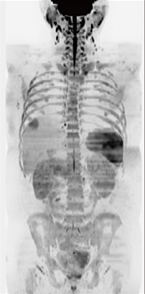

■症例1:横行結腸がん/肝転移疑い

T1WI,DIXON In/Out,2 station |

T2WI,DIXON Water,2station |

Body DWI(b=800),4station |